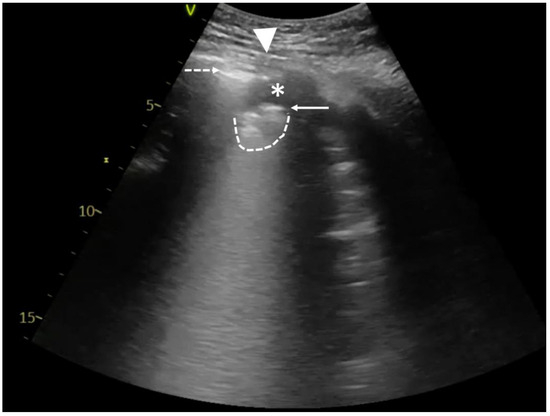

The mechanical ventilation of ARDS patients is likely to make it challenging due to high PEEP and small tidal volumes. Therefore, the absence of pleural sliding cannot be the only symptom determining the diagnosis of pneumothorax. In cases of diminished lung sliding, a high-frequency linear transducer should be used to better visualize the pleura. Alternatively, M-mode combined with real-time ECG may be useful to search for the so-called lung pulse. A “pseudo” lung pulse may result from intercostal muscle contraction in a spontaneously breathing patient, but unlike a real lung pulse, it starts above the pleural line, passes down crossing it, and does not correlate with the heart rate (Figure 1A; Video S1A) [3].

Figure 1.

Point-of-care lung ultrasound of a 59-year-old male with severe ARDS, mechanically ventilated (Bilevel; FiO2 60%; PL10 cmH2O; PH15 cmH2O). A left-sided pneumothorax occurred after pacemaker implantation. The study was performed using a 1.8–6 MHz convex probe. (A) Muscle contractions imitate lung pulse and hinder the diagnosis of pneumothorax. LUS examination revealed horizontal reverberation artifacts (dashed arrows). M-mode image shows a barcode sign with visible vertical artifacts (asterisks). Unlike a real lung pulse, the artifacts originate from the intercostal muscles (ICMs). Therefore, they start superficially to the pleural line and move down, passing the pleural line (solid arrow). Please see Video S1. (B) Lung point is a pathognomonic sign of pneumothorax and can be fully seen in Video S1B. This static image shows both pleural laminae separated from each other. As a result of pneumothorax, only the parietal pleura is visible on the left side (indicated with a dashed arrow). On the right side, a part of the lung with fragmented pleural line (solid arrow) and subpleural consolidation (dashed line) can be seen. The contact area is called the lung point (triangle).